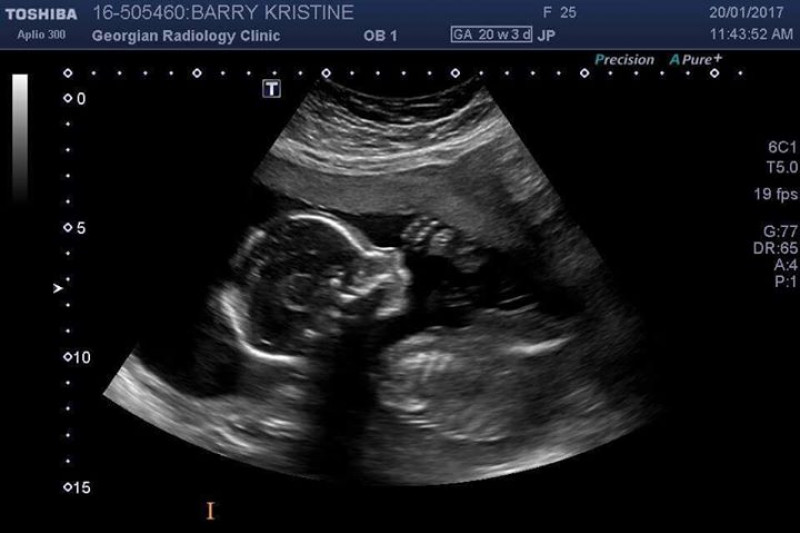

His mom, Kristine Barry, knew something was wrong when she went in for her 20-week ultrasound.

“All of a sudden, [the technician] got really quiet, and she said she needed to focus,” Barry told Global News.

The ultrasound tech went over Sebastian’s hands, his feet, his body and even revealed that the growing family was having a baby boy. But she warned them to get in touch with their family doctor straight away.